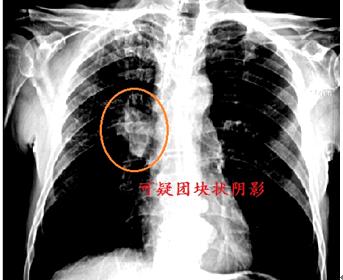

4、 肺部肿瘤

肺部肿瘤很多肺部肿瘤患者都是在体检时发现肺部有结节及肿块阴影,在医院进一步检查时发现,做到早发现、早诊断、早治疗,才能达到理想的预后效果。肺部肿瘤一般可见可疑团块阴影,患者一旦发现应及早到正规医院进行CT扫描排查恶性肿瘤的可能性。